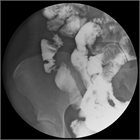

1. クローン病とは、原因不明の、口腔内から肛門周囲までの腸管のどの部位にでも発症する炎症性腸疾患の1つである。